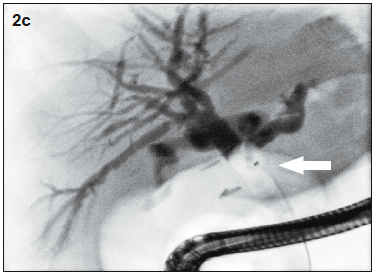

Figura 2c. Balón de deshabitación de la vía biliar intra y extrahepática

El estudio por colangioresonancia evidenció una variante anatómica biliar tipo 3 de la clasificación de Huang, ya que el conducto hepático posterior derecho drenaba en el conducto hepático izquierdo.1 Se observaron imágenes compatibles con litiasis intrahepática derecha y litiasis en el colédoco distal. La CPRE confirmó la presencia de la variante anatómica del patrón ductal hepático derecho y permitió realizar una canulación selectiva con posterior extracción de litos mediante balón y canastilla.2 El paciente tuvo una buena evolución clínica sin complicaciones.

La elección del tratamiento debe individualizarse según la anatomía del árbol biliar y la localización de los litos.3 En este caso la variante biliar fue determinante en la presentación clínica y en la planificación terapéutica. El paciente no presentó litiasis residual en los controles posteriores.